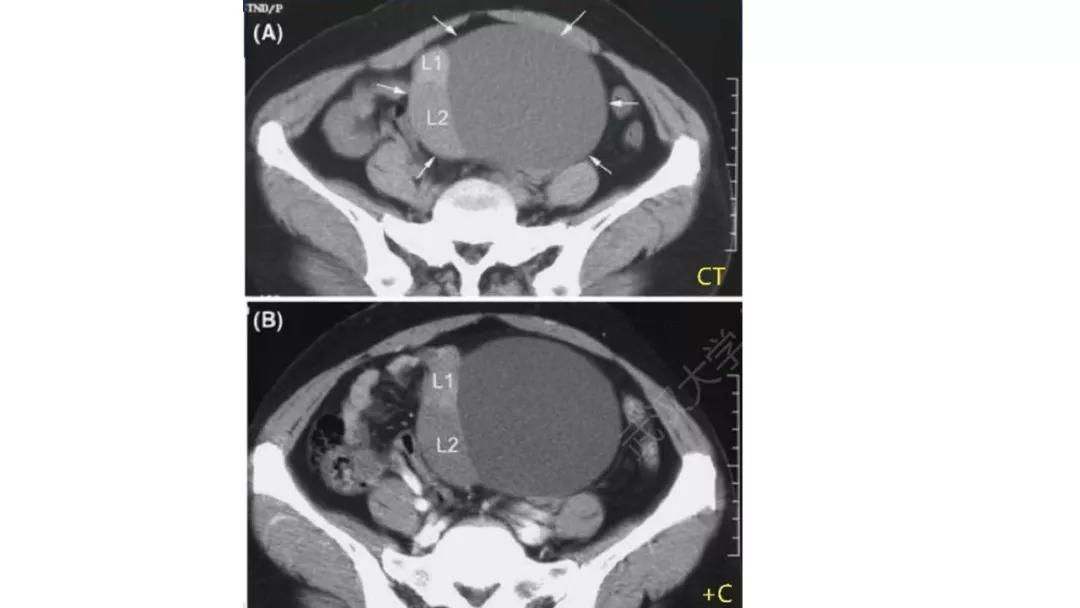

恶性者常呈实性或混杂性肿块,多数边界清楚,可伴有不规则沙粒状钙化。无性细胞瘤常为实性肿块,轻度强化,内胚窦瘤实性成分明显强化,不成熟畸胎瘤呈混杂密度。结合年龄及临床生化检查,有助于诊断。

- 纤维血管分隔呈分叶状:无性细胞瘤